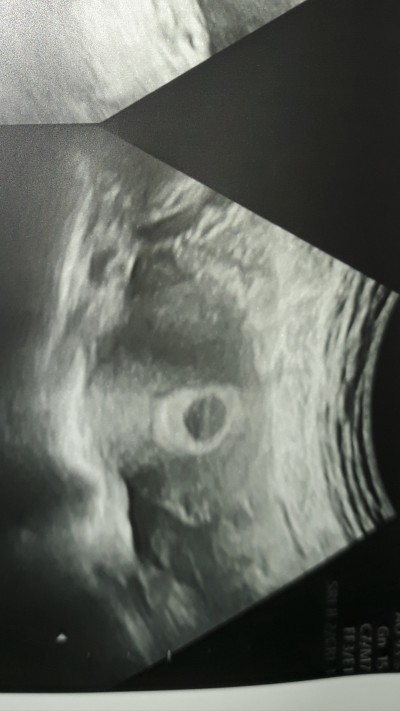

Yolk Sac Varsa Bebek Varmıdır

Yolk Sac Varsa Bebek Varmıdır.